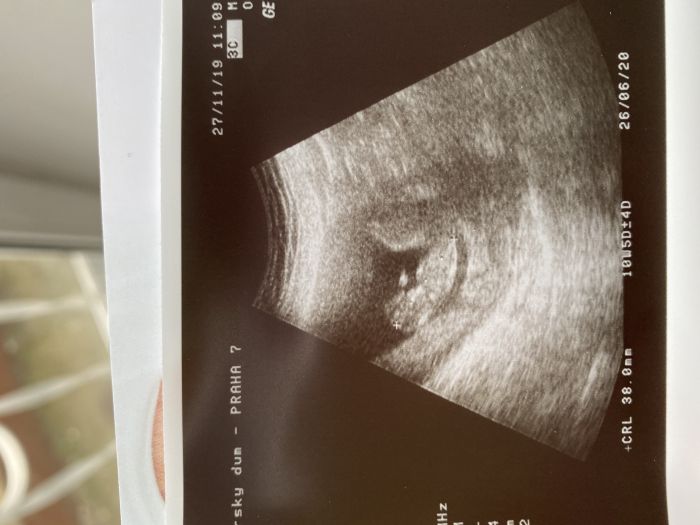

Tak dneska kontrola a mam prukazku a fotecku z ultrazvuku, kde jsme teda o tri dny vice nez dle pm... :-) nastesti taky tukam, ze je vse ok. Zitra na krev a uvidi se na screeningu 11.12. :-) preji vsem hodne zdravicka!!! :-) to je ted u vsech to nejdulezitejsi!